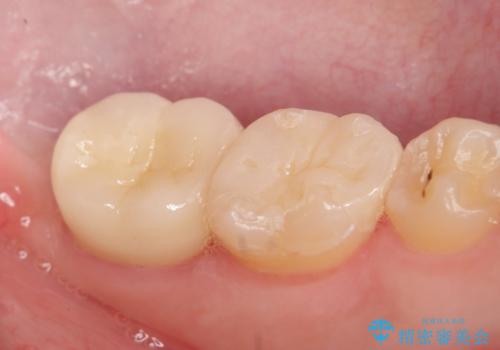

- 左下奥歯がしみるといらっしゃった方の症例です。

左下7の虫歯は深く、また歯冠高径も低かったため、歯冠長延長術を行いました。

術後歯肉の回復を待ち、左下6はセラミックインレー、左下7はオールセラミッククラウンにて補綴しました。